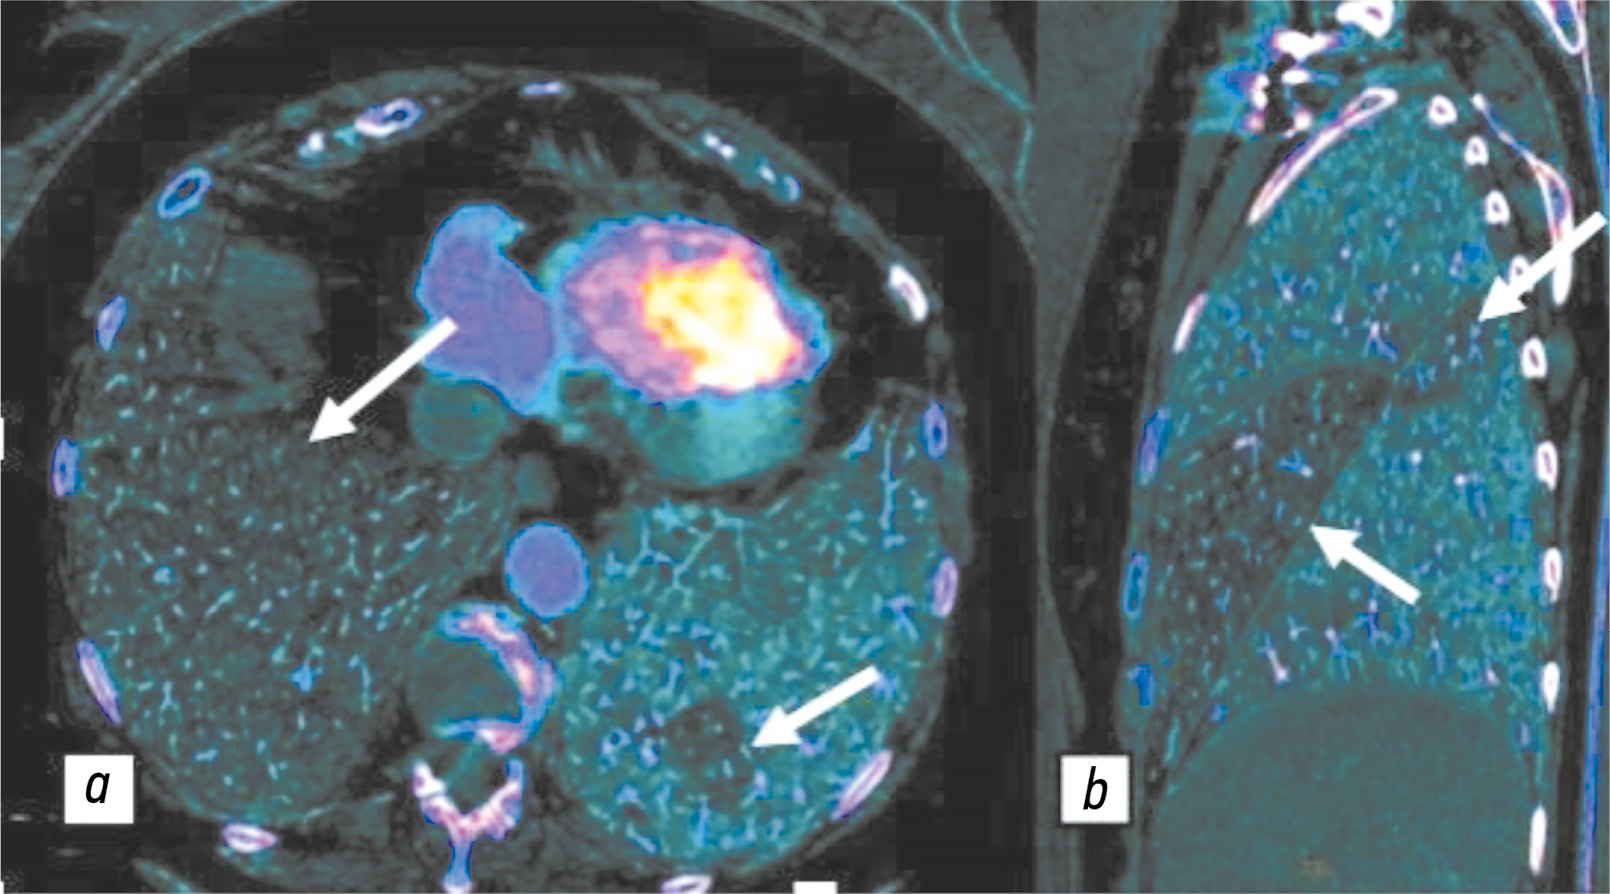

Следует отметить, что изображения, полученные с помощью двухэнергетической КТ-ангиопульмонографии, не предоставляют данные о динамической перфузии, поскольку отображают распределение йода только в определённое время (йодные карты лёгочной микроциркуляции) [44]. Перфузионные изображения, полученные с помощью данного метода, хорошо коррелируют с данными сцинтиграфии и позволяют визуализировать дефекты перфузии (рис. 3) [45–47].

Рис. 3. Цветные йодные карты перфузии, полученные с помощью двухэнергетической компьютерно-томографической ангиопульмонографии: a — дефекты перфузии нижней доли справа, локальный дефект перфузии нижней доли слева (белые стрелки); b — дефект перфузии средней доли, участок гипоперфузии S2 и S6 (белые стрелки). Публикуется с разрешения правообладателя. © ФГАУ «Лечебно-реабилитационный центр», 2018.

Йодные карты предоставляют возможность дифференцировать физиологические и патологические нарушения перфузии. Так, при гемодинамически значимой обструкции сосуда на йодных картах определяют дефекты перфузии клиновидной формы. Физиологическое снижение перфузии наблюдают при гравитационном распределении кровотока, вдоль междолевых листков плевры, в зонах артефактов от контрастного препарата в подключичной и верхней полой венах, а также в областях экскурсии диафрагмы и движения сердца. В данных ситуациях форма дефектов перфузии будет линейной или серповидной [27].

Важной особенностью двухэнергетической КТ-ангиопульмонографии является способность демонстрировать зоны гипоперфузии при отсутствии инфарктпневмонии, что выгодно отличает данный метод от традиционной компьютерной томографии. При инфаркте в периферических отделах определяют зоны отсутствия контрастирования клиновидной формы с уплотнением лёгкого, визуализируемые в лёгочном окне. Участки сниженного контрастирования на перфузионных изображениях при ТЭЛА без развития инфаркт-пневмонии определяют без сопутствующего уплотнения в лёгочном окне [28].